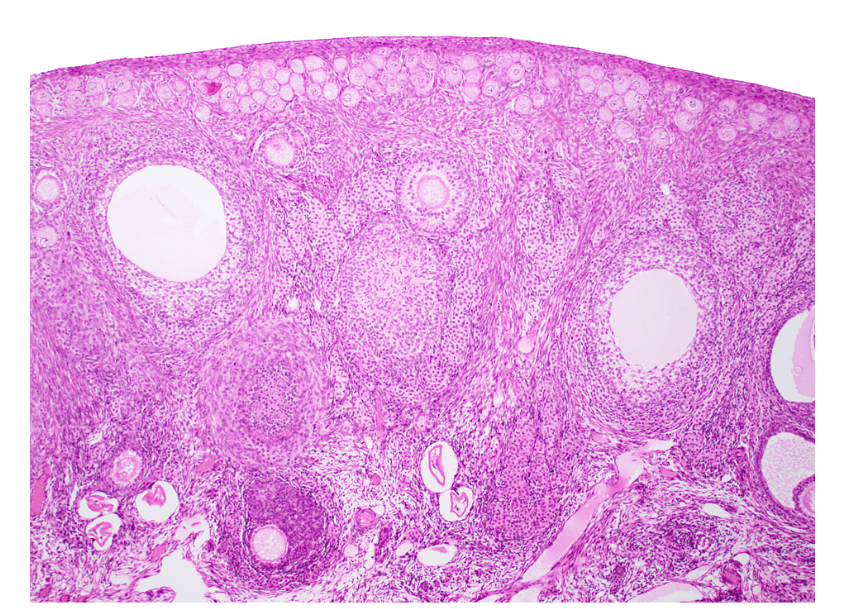

ovary (sagittal section)

primordial follicles

primary follicle

secondary follicle

antrum

tunica albuginea